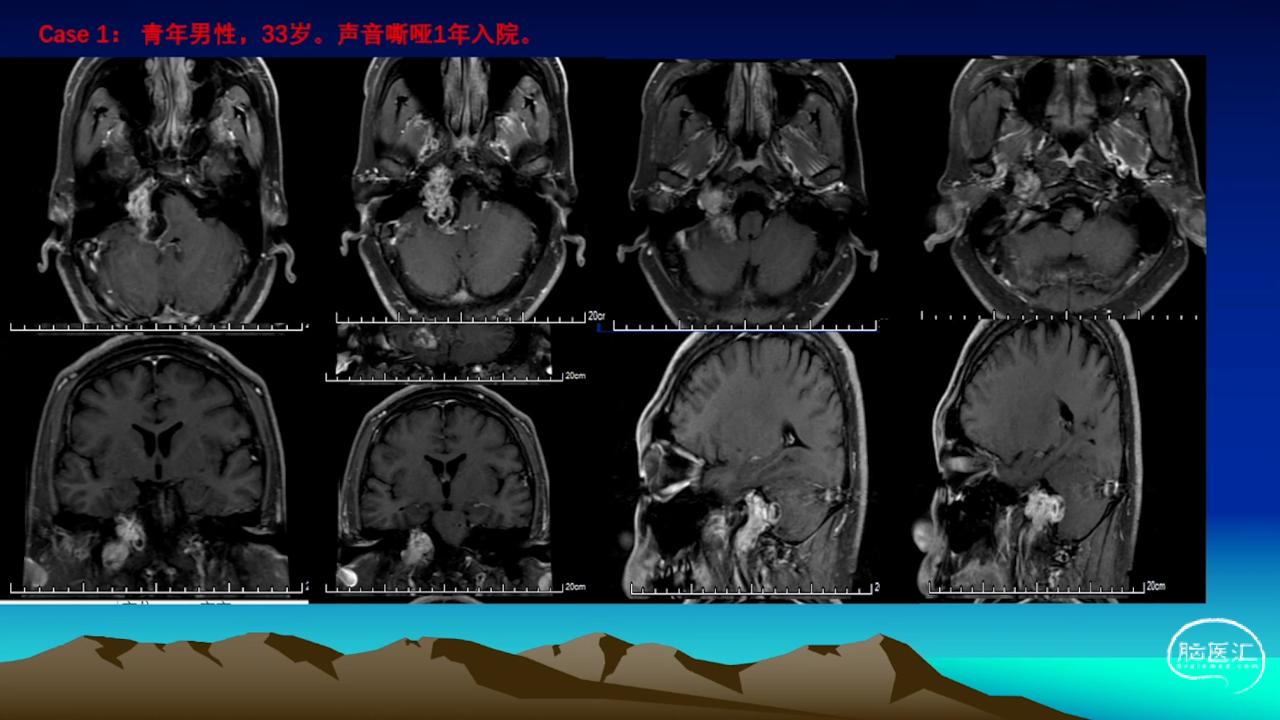

颈静脉孔区肿瘤充分显露是硬道理。肿瘤越大,工作通道越宽。颈静脉孔扩大越明显,开放颈静脉孔越容易。

卜博教授:颈静脉孔区肿瘤:解剖及156例经验